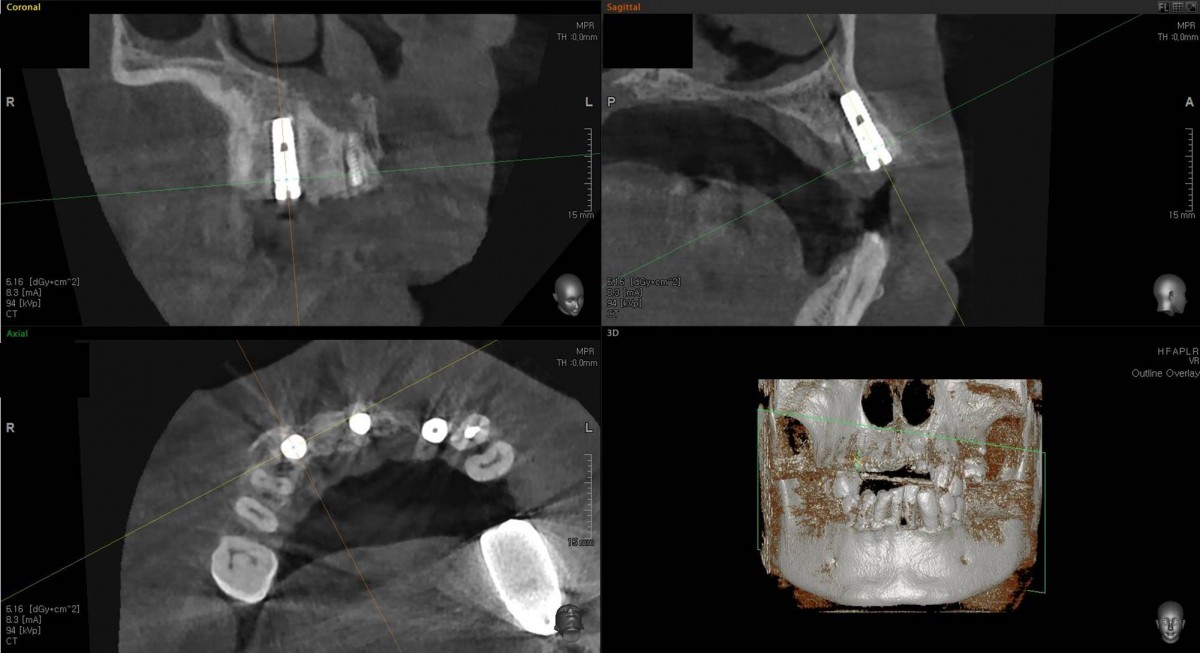

In the anterior maxilla, implant-supported fixed partial denture.

<GCpbc> A 58-year-old male is a patient undergoing implant installation in various parts. The old Br of the anterior maxilla has fallen

off and it is no longer possible to maintain it even temporarily, so a

treatment plan for the anterior teeth was made.